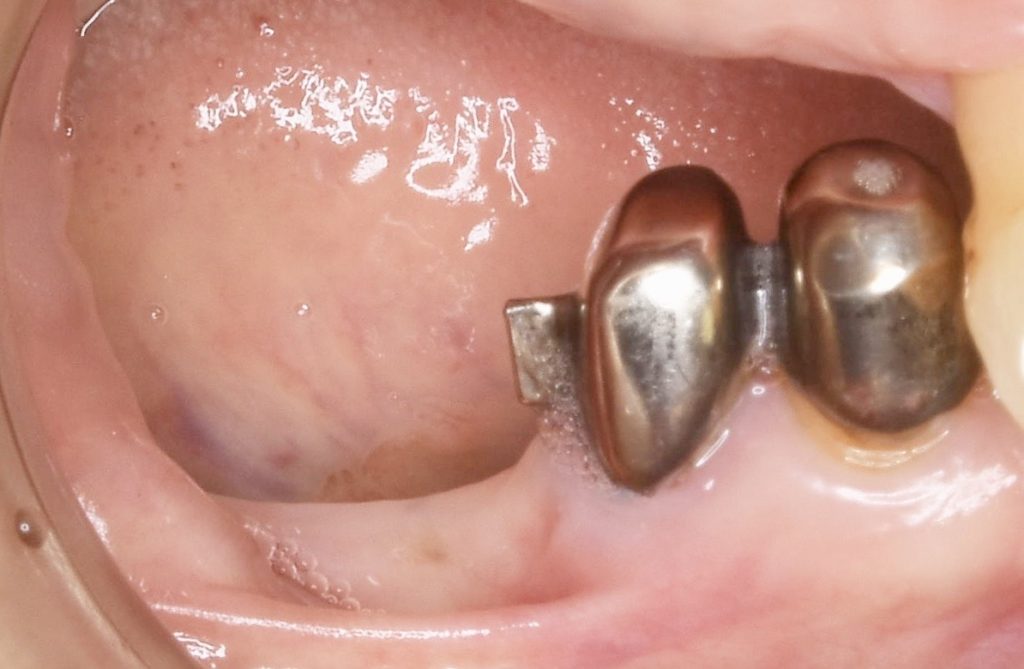

下の症例は、83歳の女性になります。

長年、入れ歯を装着されていたのですが、アタッチメントを装着している歯が大きな負担により歯根破折を起こして咀嚼不全となりました。

高齢の為、早期の咀嚼機能の回復を目指しショートインプラントを用いた咬合機能の回復を目指しました。